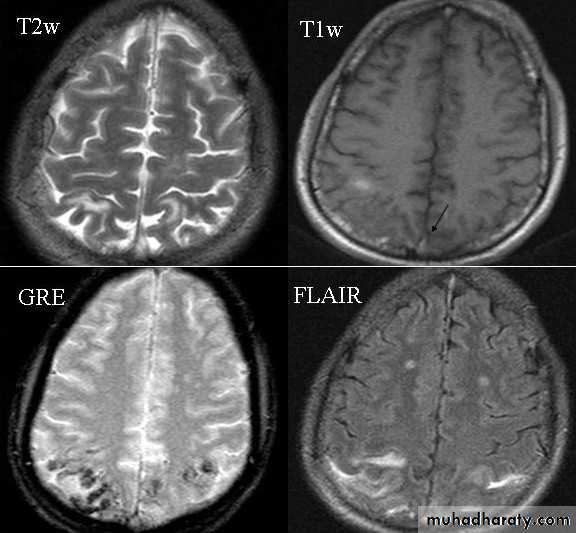

MRI:

* Initial diagnosis of SAH* detect completely thrombosed aneurysm

* limited in acute cases